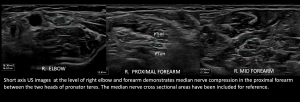

Elbow and Forearm: The median nerve then enters the cubital fossa and courses beneath the bicipital aponeurosis, aka lacertus fibrosus, medial to the brachial vessels. In the proximal forearm, it passes between the humeral and ulnar heads of the pronator teres (PT), forming the pronator tunnel. After exiting the pronator teres, it then enters under the flexor digitorum superficialis (FDS) fibrous arch, aka the sublimis bridge. It then traverses between the flexor digitorum superficialis (FDS) and flexor digitorum profundus (FDP) musculature [3-5].

The potential sites of proximal nerve compression along its usual anatomical course include under the lacertus fibrosus, along the pronator tunnel, and under the FDS arch, which are illustrated

1.Entrapment Neuropathies at Proximal Forearm:

Fig 7: COMPRESSION UNDER LACERTUS FIBROSUS - Compression at Pronator Tunnel

Fig 8: COMPRESSION AT THE PRONATOR TUNNEL - Compression at Flexor Digitorum Superficialis (FDS) Arch